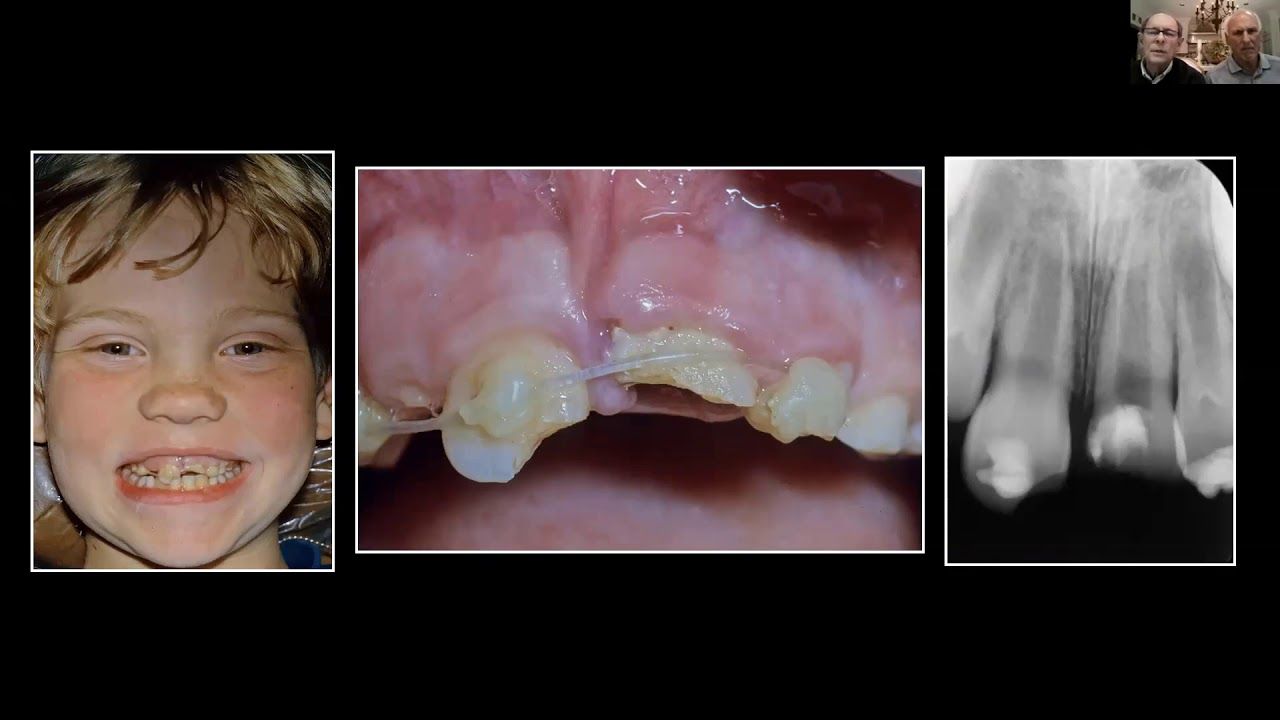

Dr. Dave Mathews and Dr. David Steiner show us unique strategies for preserving the alveolar ridge in children whom have suffered traumatic injury.These conservative strategies will help your colleagues as well as your patients.